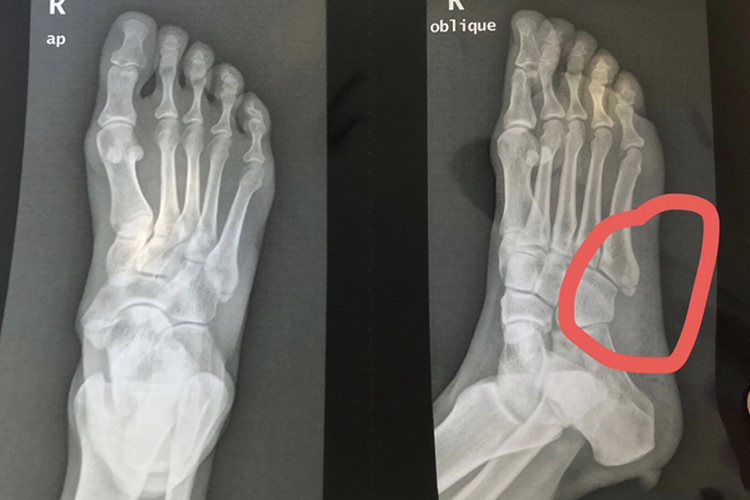

跖骨属于长骨,共有5块,自足内侧至外侧依次称为第1-5跖骨。跖骨的近端为基底部,中部为体部,远端为头部,是人体站立、行走及负重的重要组织。患者出现右足第5跖骨基底部骨折,可表现为局部疼痛不适、发红、肿胀,尤其以足外侧明显,无法下地行走。体格检查时可见伤足外侧肿胀、淤血,足部主、被动活动明显受限。足X线正、斜位片可观察有无第5跖骨基底部骨折,并观察有无足部其他部位骨折。

右足第5跖骨基底部骨折患者需注意患肢制动,还可适当冰敷,局部加压包扎,抬高患肢,局部肿痛症状缓解后可尝试热敷,渐进性负重锻炼。若右足第5跖骨基底部受损较为严重、骨折移位明显,或是经非手术治疗后出现骨折处不愈合、畸形愈合的患者,建议手术复位内固定治疗。